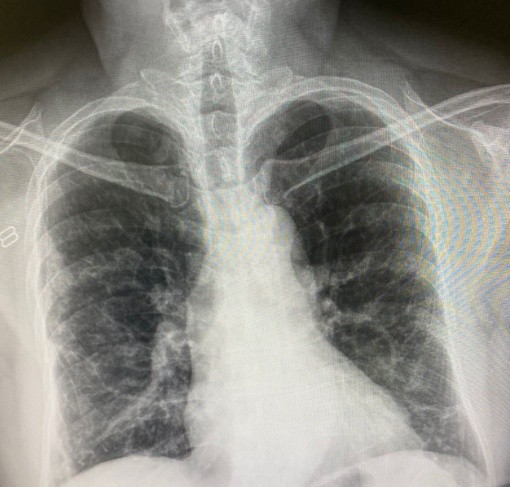

قال أخصائي أمراض الرئة عضو اللجنة الايطالية العلمية لطوارئ وباء فيروس كورونا، لوكا ريكيلدي، إنه وجدت "نسبة صغيرة من المرضى الذين لا يزال لديهم علامات التليف الرئوي حتى عند خروجهم من المستشفيات، ولا نعلم ما إذا كان سيزول بمرور الوقت أم لا".

وأضاف: "لدينا فقط أدلة متداولة نظرا لقصر الوقت مقارنة بمتوسط ​​طول فترة العلاج في المستشفى للمرضى في وحدات العناية المركزة الذين تعافوا. ولكن في الصين قاموا بالفعل بدراسات حول ذلك، واكتشفوا أن ثلث أولئك الذين دخلوا العناية المركزة يعانون من فشل تنفسي حتى عند خروجهم من المستشفيات"، وفقا لصحيفة "لاريبوبليكا" الإيطالية

ويرى أخصائي أمراض الرئة أنه "بشكل عام ، بعد أسبوعين أو ثلاثة أسابيع من التنبيب (عبر جهاز التنفس الصناعي) هناك بعض الأضرار التي يمكن أن تحدث في الرئة. ولكننا لا نعلم بالضبط الأسباب ولا حتى مدى تطورها".